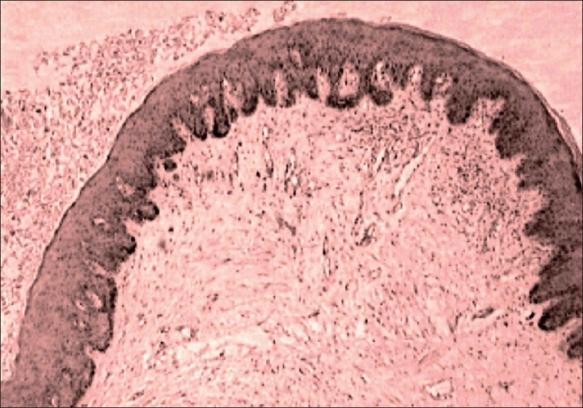

Seborrheic keratosis of the penis is a rare entity. It has been mistaken as genital warts and differentiation is only made on histopathology. We are reporting a case presenting as multiple giant polypoidal lesions on the penile skin for the last 20 years. Seborrheic keratosis should be considered in the differential diagnosis of pedunculated lesions of the penis. The histopathology after shave excision will be diagnostic.